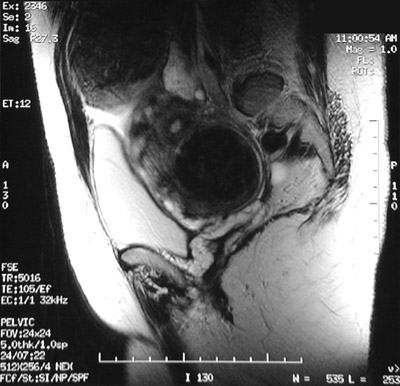

| This T2 weighted FSE MRI scan of the pelvis in sagittal view reveals a large nodular uterus containing leiomyomata. One large leiomyoma is seen protruding subserosally from the upper fundus, while another leiomyoma is seen intramurally in the lower portion of the uterus compressing the bladder anteriorly. |